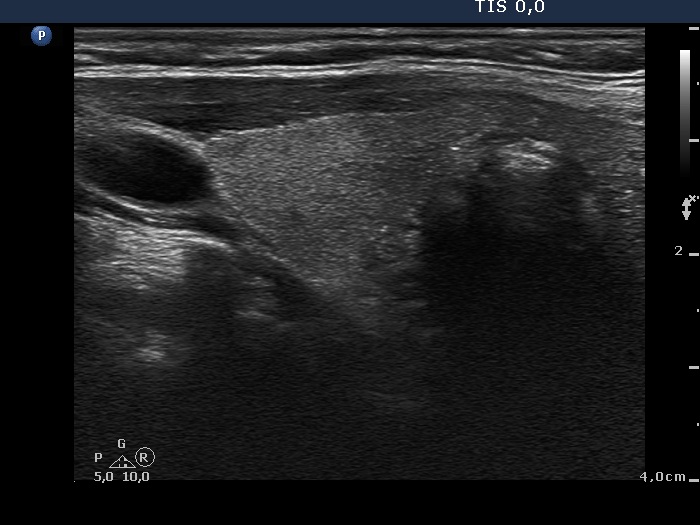

Study on 100 consecutive patients with thyroid nodule - case 050 (ultrasonographic picture 2)

Right lobe, longitudinal scan.